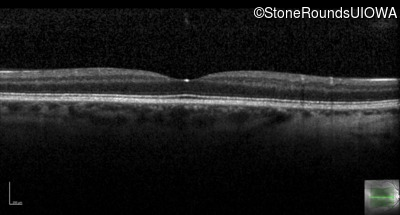

Optical Coherence Tomography - Right - 20/200 -1

Exemplar / OCT Stack

OCT Stack